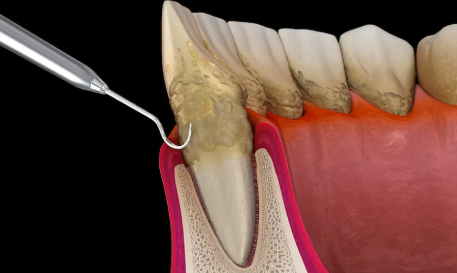

Gum Treatments

(Scaling / Flap Surgery / Laser Gum Therapy / Grafting / Root Planing)

Treats gum disease with effective and targeted care. Helps restore the health of the gums and surrounding tissues. Improves overall oral hygiene and long-term dental wellness. Reduces gum inflammation, swelling, and discomfort. Promotes faster healing and a healthier gum structure. Strengthens the gums to support the teeth more effectively. Contributes to fresher breath and improved daily confidence.